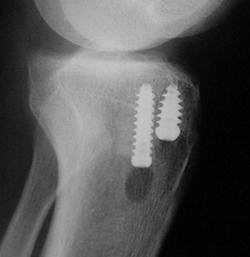

Planlamada önceki kesiler, kullanılan implantlar, ilk tünellerin yeni açılacak tünellerle ilgisi değerlendirilmeli, ilk implantların çıkartma setleri bulundurulmalıdır. İlk tüneller çok genişlemiş ve yeni greftin yerleşimini ve tespitini engelliyorsa iki seanslı cerrahi gerekli olabilir. İlk seansta implantlar çıkartılır ve tüneller greftlenir, sonra ikinci seansta revizyon cerrahisi yapılır. Bunun için oto veya allogreft hazırlığı olmalıdır. Revizyonda kullanılacak tendon grefti seçimi önemlidir. Hastada daha önce kullanılmayan otolog greft kaynakları ilk tercih olmalıdır. Bu mümkün değilse karşı diz ya da allogreft tercih edilebilir.Cerrahi teknik

Revizyon cerrahisi diz ekleminin artroskopisi ile başlar. İlk cerrahideki greft artıkları temizlenir, eşlik eden meniskal ve kondral patolojiler düzeltilir. İlk cerrahi sırasında kullanılan implantlar, yeni tünelleri engellemiyorsa çıkartılmamalıdır. Özellikle yeni tünele yakın olan implant çıkartılırsa, tünel duvarları zayıflayabilir. Tibial tarafta çoğunlukla daha medialden bir tünel açılabilir.

Tünel genişlemesi varsa, büyük kemik bloklu allogreft veya greftleme sonrası iki seanslı cerrahi düşünülmelidir. Femoral tünel ilk cerrahide çoğunlukla önde açıldığı için arkaya ve inferiora doğru ikinci bir tünel mümkündür. Standart tespit yöntemlerine ek olarak eklemden uzak ilave tespit yöntemleri gerekli olabilir. Genişlemiş tünellerde eklemden uzak tespit yapılırsa, tünel içinde hareketi azaltmak için biyoçözünür vida veya kemik grefti eklenebilir.